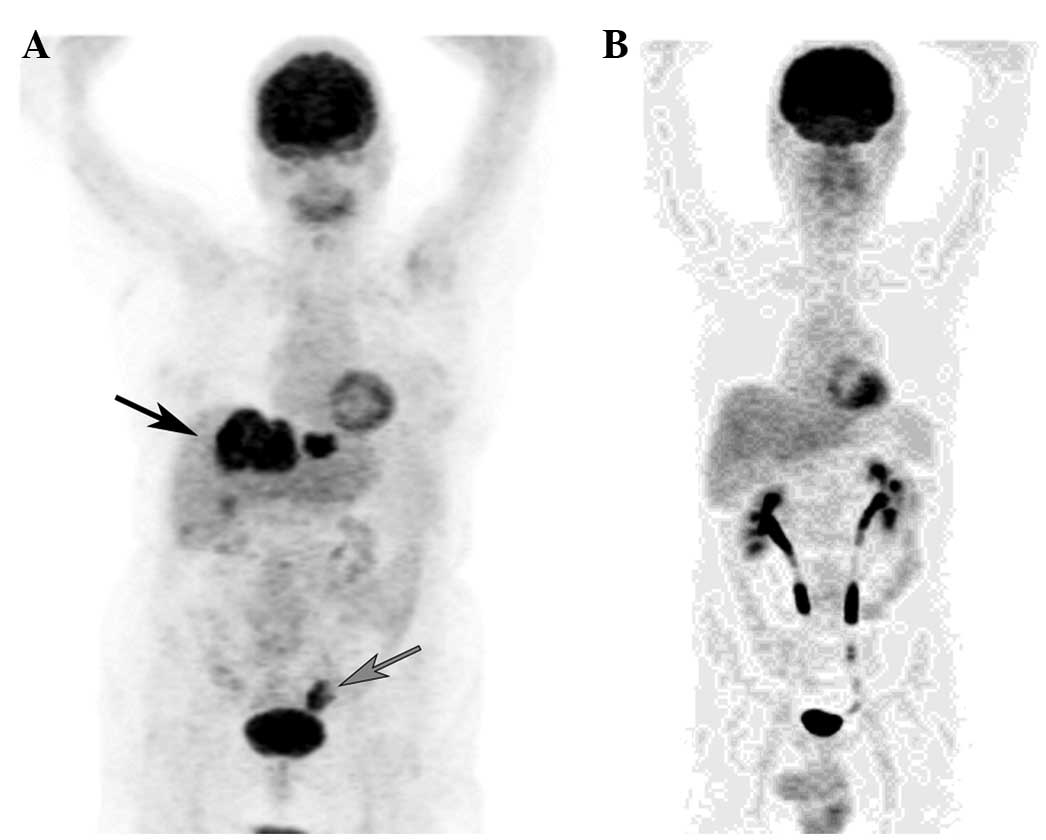

At the PET/CT examination, 13 out of the 100 subjects examined were positive for LR only, 7 were positive for LR and LN, 2 presented with LR and liver lesions, 2 with LR and liver and peritoneal lesions, and 2 with LR and lung lesions. Furthermore, 2 patients were positive for LR, LN and adrenal lesions, 4 presented with lesions in the LNs only and 7 with lesions in the LNs and lungs. Lung lesions only were detectable in 5 subjects, liver lesions only were detectable in 11 subjects, and lung and liver lesions were detectable in 9 subjects. Representative PET images of recurrence-positive and recurrence-negative cases are shown in Fig. 2.

Figure 2.

(A) Representative MIP image of a 67-year-old female subject with a previous history of CRC (T3N1M0) treated with surgery and chemotherapy. Pathological fluorodeoxyglucose uptake is detectable in the liver (black arrow) and the iliac lymph nodes (grey arrow). CEA and CA 19–9 levels were 29.38 ng/ml and 7.68 U/ml, respectively. (B) Representative MIP image of a 57-year-old male subject with a previous history of CRC (T2N0M0) treated with surgery, where no pathological findings are detectable. Serum CEA and CA 19–9 levels were 2.8 ng/ml and 35.9 U/ml, respectively. CEA, carcinoembryonic antigen; CA 19–9, carbohydrate antigen 19–9; MIP, maximum intensity projection; CRC, colorectal cancer.